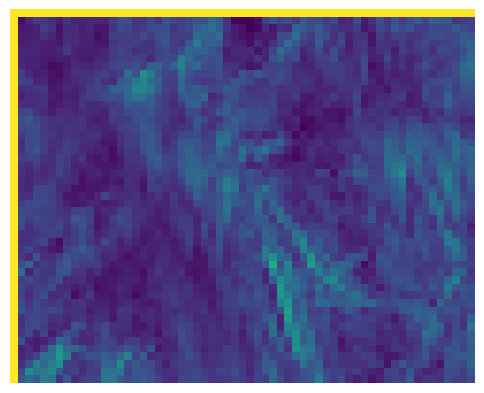

(e) NPB-REC Std.

Figure 3: Reconstructions results. Rows 1 and 3: Examples of comparing the ground truth (GT) fully sampled image to the reconstructed images obtained by the three models (1-3), NPB-REC, baseline, E2E-VarNet trained with Dropout, and the NPB-REC std. map at accelerations R=4𝑅4R=4, R=8𝑅8R=8, respectively. Rows 2 and 4: The corresponding annotated ROIS of Nonspecific white matter lesions.

Fig. 3 presents examples of reconstruction results obtained by (1) our NPB-REC approach, (2) the baseline, and (3) Monte Carlo Dropout, for equispaced masks with two different acceleration rates R=4𝑅4R=4 and R=8𝑅8R=8. The reconstructed images predicted by the three models are smoother than the reference image. This is due to the fact that all the models were trained with SSIM loss, which tends to produce overly smooth reconstructions while preserving the diagnostic content and the anatomical features Sriram et al. (2020a). These images can be enhanced by dithering the image by adding a small amount of random Gaussian noise to produce a more textured reconstruction, as proposed in Sriram et al. (2020b).

Table 1 presents the mean PSNR and SSIM metrics, calculated over the whole inference set, for the three models. Our NPB-REC approach achieved significant improvements over the other methods in terms of PSNR and SSIM (Wilcoxon signed-rank test, pmuch-less-than\ll1e-4, except for SSIM values in line W, R=4𝑅4R=4 where they are roughly the same for NPB-REC and Baseline). The improvement in the reconstruction performance can be noted both quantitatively from the metrics, especially for masks with acceleration rate R=8𝑅8R=8, and qualitatively via the images of annotations, where our results show less smoothness than those obtained by Dropout.